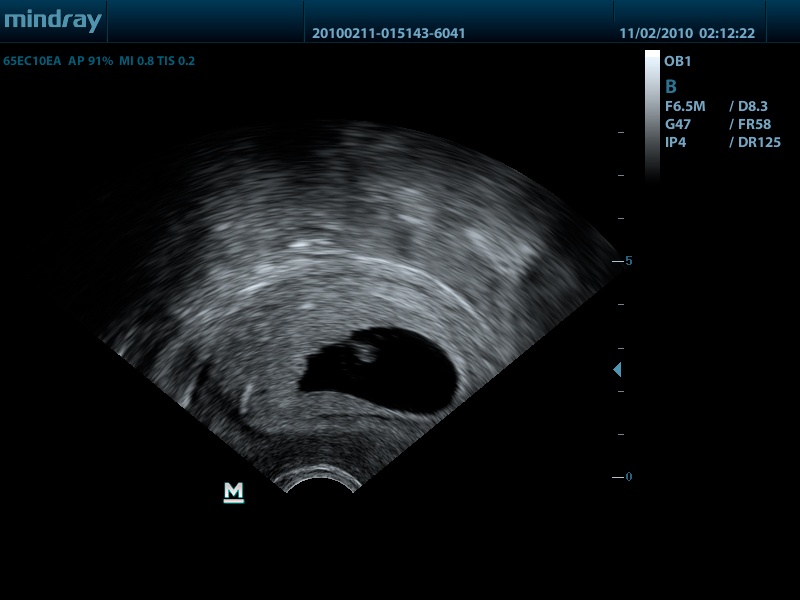

- Внутриполостной датчик 65EC10EA, 3.0 - 12.5 МГц, радиус кривизны 10 мм